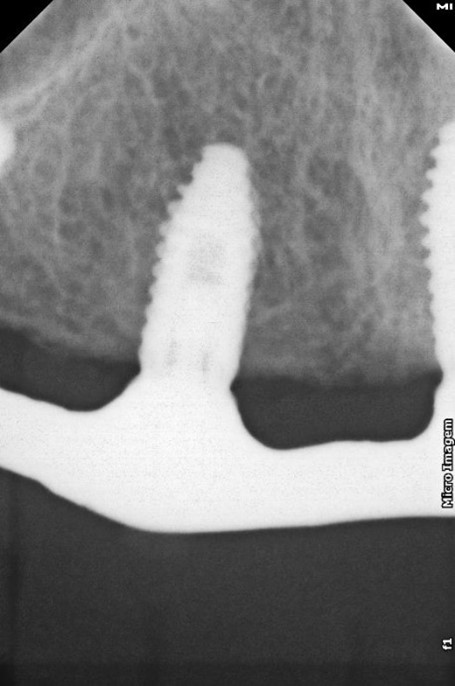

Fig. 2 – Radiografia inicial

Na análise radiográfica, constatou-se pneumatização do seio maxilar direito em direção ao pilar canino. No lado esquerdo, a extensão da pneumatização poderia inviabilizar a realização da técnica sem enxertos ósseos. Para garantir a instalação precisa e segura do implante, foi realizado um acesso lateral à janela do seio maxilar, permitindo o tratamento da parede anterior do seio com uma sonda para determinar a posição ideal do implante distal. Aproveitou-se o máximo de osso disponível, tangenciando o seio maxilar e eliminando a necessidade de enxertos ósseos. Foi escolhido o sistema Vezza da FGM, devido a geometria que fornece alta estabilidade primária e oferece conexão hexagonal externa universal, ou seja, bastante versátil.